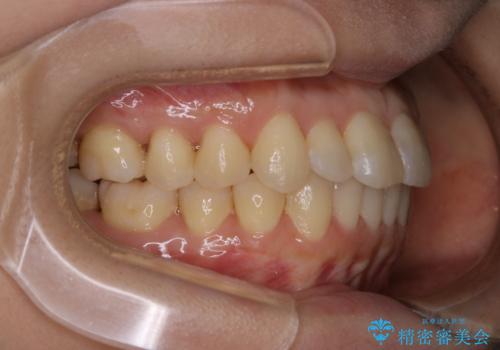

上下左右の歯を後ろに動かして歯を並べるスペースを確保し、内側に入っていた歯を綺麗に並べ、前歯の中心もお顔の中心に合うようにしました。

矯正用アンカースクリューを埋入し、上下左右の歯を後ろに動かすことで歯を並べるスペースを作りました。

元々内側に倒れていた右下の奥歯は、ゴムかけを追加で行っていただくことによりしっかり起こすことが出来ました。

歯並びが綺麗になったことでモチベーションが上がり、銀歯からセラミックへのやり替えも行っております。